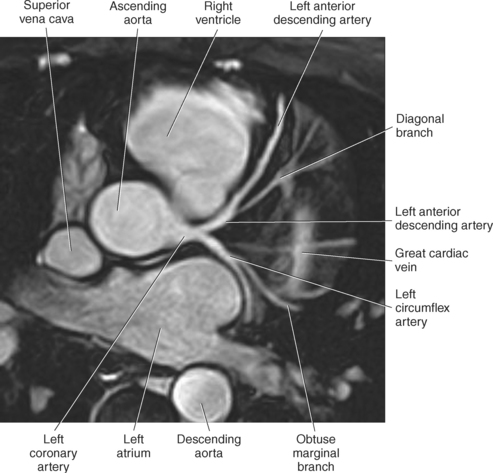

The two main coronary arteries are the first vessels to branch off the ascending aorta (Figures 6.91 and 6.92). The right coronary artery arises from the base or root of the aorta (right aortic sinus) and passes anteriorly between the pulmonary trunk and right atrium to descend in the coronary (atrioventricular) groove. As it reaches the diaphragmatic surface, it gives off a right marginal branch that runs toward the apex of the heart. The right coronary artery then turns to the left and enters the posterior interventricular groove, where it gives off the posterior interventricular branch (posterior descending artery). The posterior interventricular branch continues to descend along the interventricular groove toward the apex, where it anastomoses with the left anterior descending artery of the left coronary artery. The right coronary artery and its branches supply the right atrium, right ventricle, interventricular septum, and the sinoatrial (SA) and atrioventricular (AV) nodes. It also supplies a portion of the left atrium and ventricle (Figures 6.92 through 6.96). The left coronary artery arises from the left aortic sinus and passes to the left between the pulmonary trunk and left atrium to reach the coronary groove (Figures 6.91 and 6.92). Soon after reaching the coronary groove, the left coronary artery divides into the circumflex and left anterior descending (interventricular) arteries. The circumflex artery winds around the left border of the heart to the posterior surface, where it gives off the left marginal artery. The left anterior descending artery (LAD) descends in the anterior interventricular groove toward the apex of the heart, where it reaches the diaphragmatic surface to anastomose with the posterior descending artery. The left coronary artery and its branches supply the interventricular septum, including the AV bundles, and most of the left ventricle and atrium (Figures 6.97 through 6.99).

Most of the venous return from the heart is carried by the coronary sinus as it runs along the posterior section of the coronary sulcus and terminates in the right atrium immediately to the left of the inferior vena cava. The coronary sinus is a wide venous channel situated in the posterior part of the coronary sulcus and is the main vein of the heart (Figures 6.100 through 6.102). Its tributaries include the great, small, and middle cardiac veins; the left posterior ventricular vein; and the oblique vein of the left atrium. The great cardiac vein, the main tributary of the coronary sinus, arises near the apex of the heart and ascends in the anterior interventricular groove along with the anterior interventricular artery to the base of the ventricles. It receives blood from the left posterior ventricular vein and the left marginal vein before emptying into the coronary sinus. The small (right) cardiac vein runs in the coronary sulcus between the right atrium and ventricle and joins the coronary sinus from the right side. It receives blood from the right atrium and ventricle. The middle (posterior) cardiac vein commences at the apex of the heart and ascends along the posterior interventricular groove to the base of the heart, where it drains into the coronary sinus near the drainage site of the small cardiac vein. It receives blood from the posterior surface of both ventricles. The left posterior ventricular vein carries blood from the posterior wall of the left ventricle as it runs along the diaphragmatic surface of the left ventricle to drain into either the great cardiac vein or the coronary sinus. The oblique vein of the left atrium, a small vessel, descends obliquely over the posterior wall of the left atrium and enters the left end of the coronary sinus. Two small anterior cardiac veins drain directly into the right atrium (Figure 6.100).